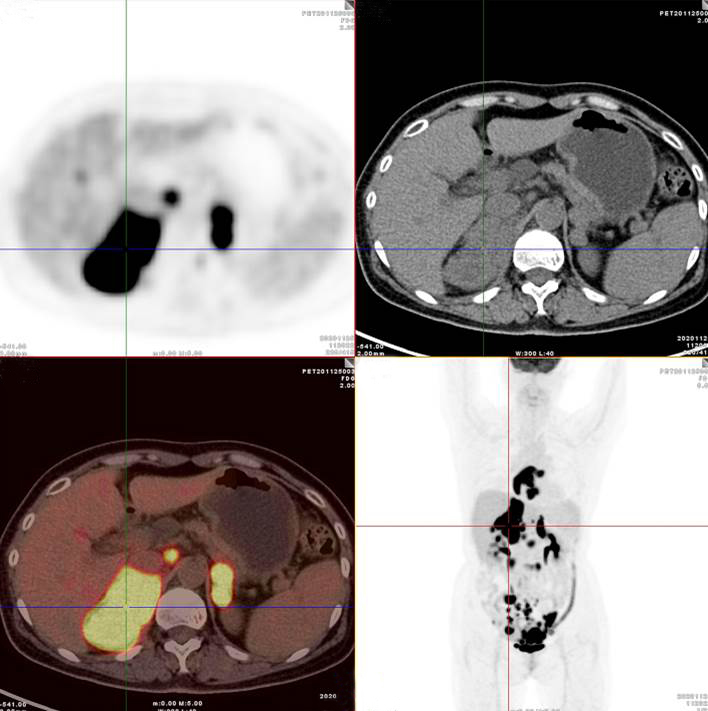

雙側(cè)腎上腺病灶、腹膜后淋巴結(jié)放射性攝取明顯增高

胃、雙腎上腺病灶、腹膜后淋巴結(jié)放射性攝取明顯增高